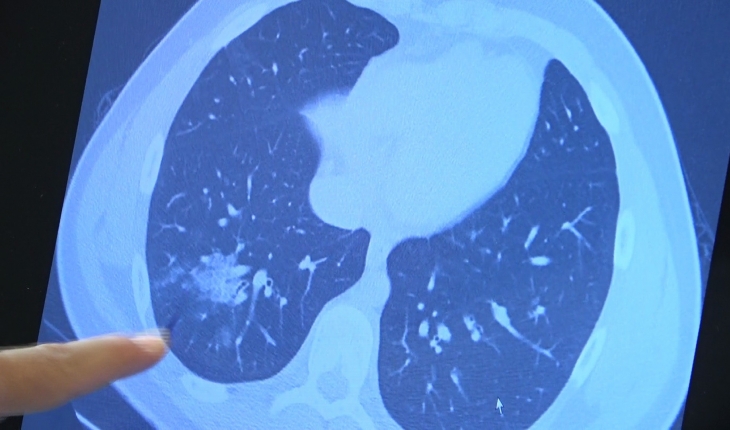

Bazı vatandaşlar hâlâ aşı olmakta tereddüt etmeye devam ederken korona virüs çocuk grubundaki hastaları da etkilemeye başladı. VM Medical Park Samsun Hastanesi Göğüs Hastalıkları Kliniği’nden Prof. Dr. Şevket Özkaya ise aşı olabilecek yaş grubundaki çocukların bir an önce aşılanması gerektiğine vurgu yaptı. 14 yaşında, kronik rahatsızlığı olan ve akciğerlerinde tahribattan dolayı ciddi öksürük, ateş ve nefes darlığı çeken bir hastanın akciğerlerini inceleyen Prof. Dr. Özkaya, "14 yaşındaki kronik rahatsızlığı mevcut olan bir genç hastamızda ciddi akciğer tutulumları var. Her iki akciğerinde de yaygın buzlu cam ve konsolidasyon alanları var. Bu yaştaki çocuklarda beklemediğimiz bir durumdur. Okullarımızda da bu risk var. Okullarımızın açık kalmasının ve sağlık sistemimizin kitlenmemesi için mutlaka aşı olmalıyız. Çocuklarımıza rol model olmalıyız. Şu anda hastanelerimiz hastalara yetişebiliyor. Yatak sayımız yeterli. Ancak kontrollü sosyal hayatımızı düzene sokmadıkça ve aşı olmadıkça, gelecekte hastanelerde yatak sayısı sıkıntısı çekebiliriz" dedi.